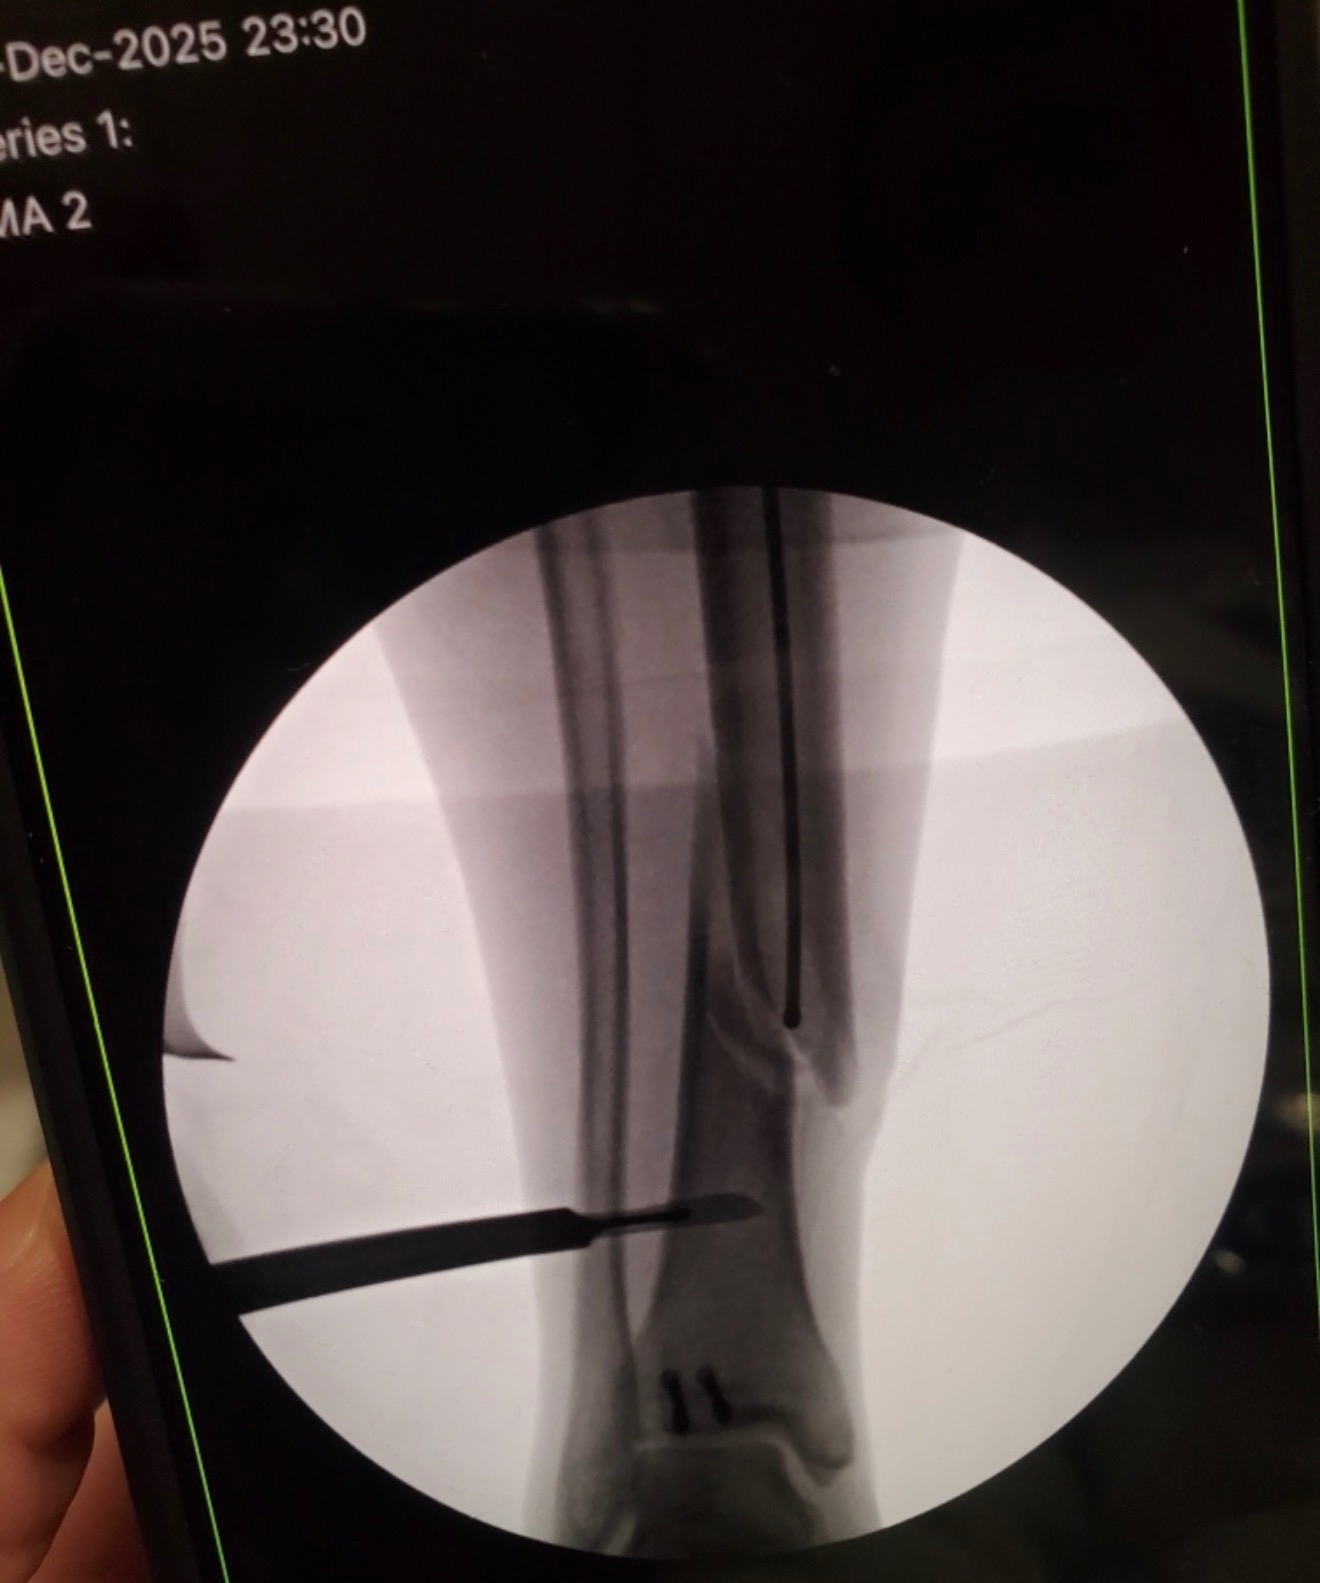

We are reaching out during an incredibly difficult and unexpected time for our family. My stepdad, Joseph, was recently involved in a serious motorcycle accident after hitting a deer at approximately 65 miles per hour. We are beyond grateful that his injuries were not life-threatening, but he did suffer a severe leg injury that required surgery, including rods placed in his leg and screws in his ankle.